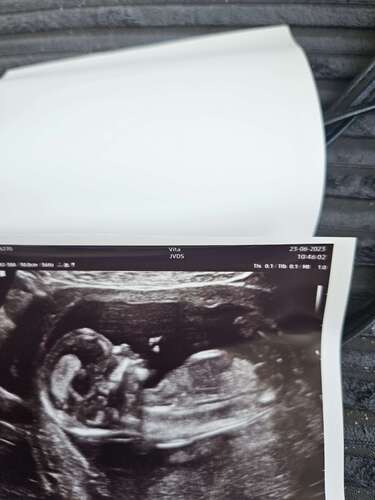

Iemand een idee wat het zou zijn?🩷💙 op deze echo was ik 15+2🤗

Ik denk een jongen